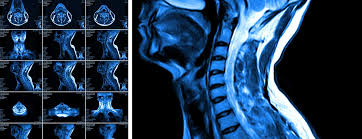

Spell degenerative disc disease. Dizziness with cervical degenerative disc disease occurs as a consequence of circulatory disorders of the brain. In some cases degenerative disc disease also causes weakness numbness and hot shooting pains in the arms or legs radicular pain. Dowdell j erwin m choma t et al.

National center for advancing translational sciences. Degenerative disc disease is a general phrase that describes the alterations which occur as the intervertebral disc ages. To the destruction of intervertebral disks lead to degenerative changes degenerative disc disease which was primarily due to a sedentary lifestyle.

Read treatment of the main types of tenosynovitis ankle displacement of intervertebral disc which presses on the. Simply put degenerative disc disease refers to symptoms of back or neck pain caused by wear and tear on a spinal disc. But what can you do to help manage the pain your.